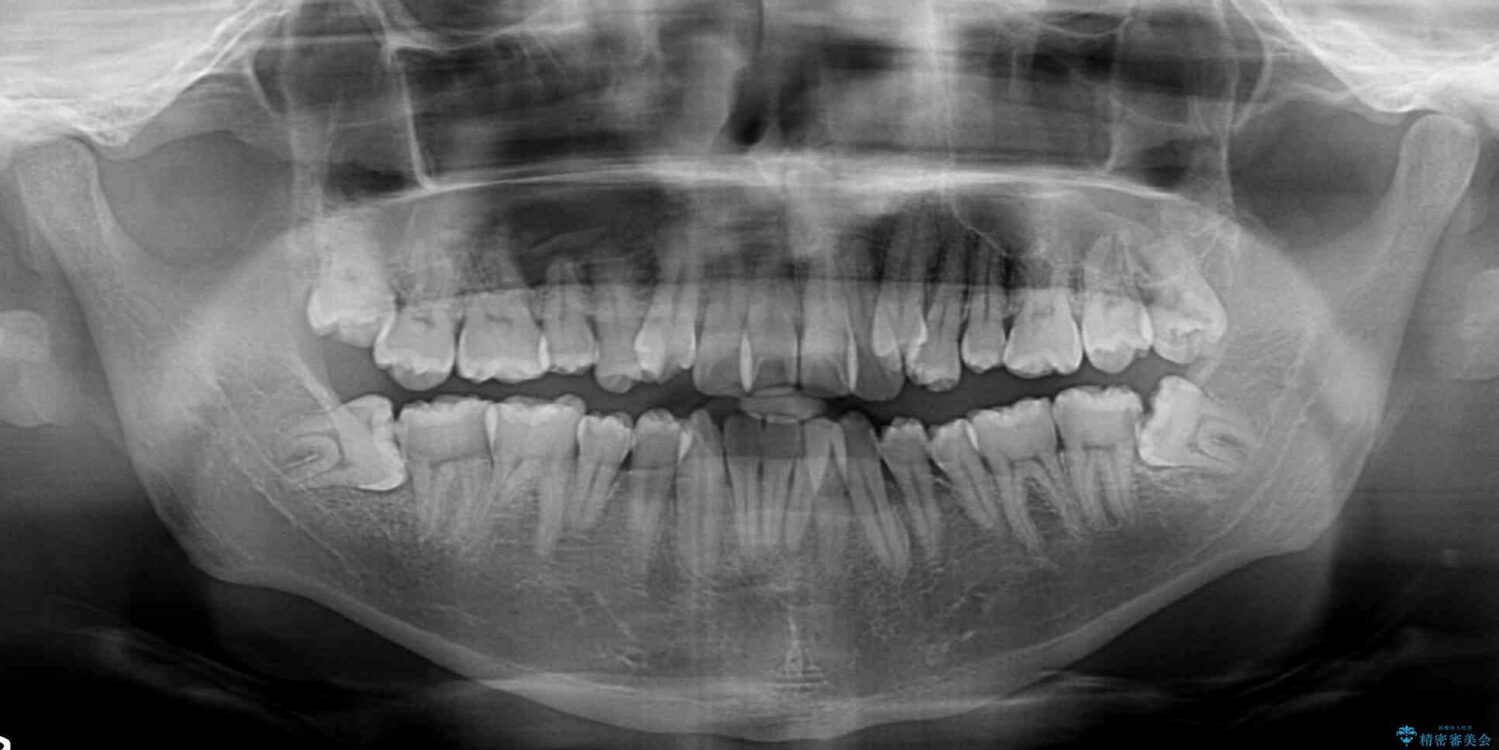

八重歯と前歯のクロスバイトを改善したいとのことで来院された患者様です。

デコボコの程度は強かったのですが、口元の突出感はなかったため、非抜歯矯正としました。

治療前

• 八重歯とクロスバイト 目立たないワイヤー装置で矯正治療 治療前画像